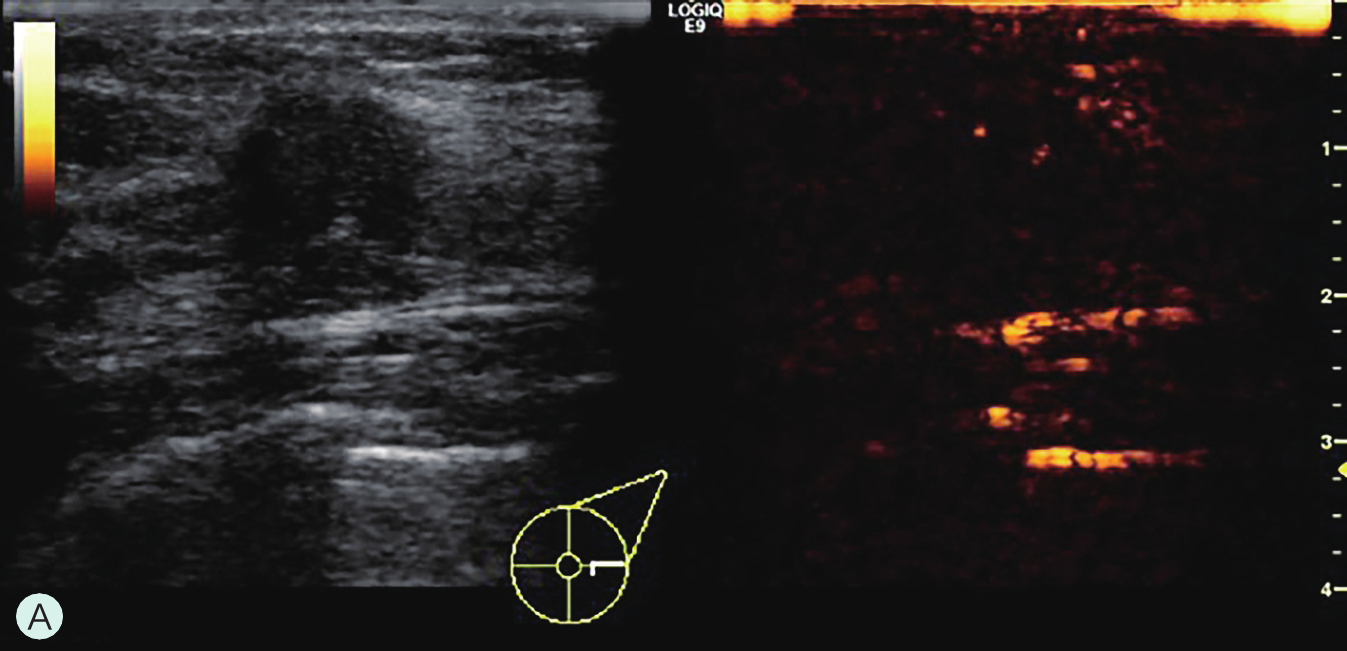

图2-2-1 确定造影病灶

A.病灶二维图像;B、C.病灶CDFI图像;D.同侧腋窝淋巴结情况;E.病灶弹性成像图像